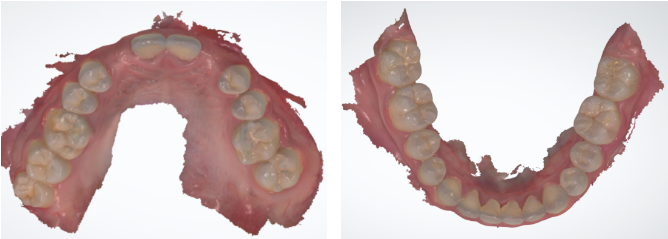

椅旁口内扫描

数字化软件进行微笑美学设计

将二维效果转变成三维效果,设计13-23的美学效果,并打印出模型

在口内进行展示

根据最终的美学蜡型效果进行椅旁种植导板设计

根据种植体位置,设计带翼预成临时冠